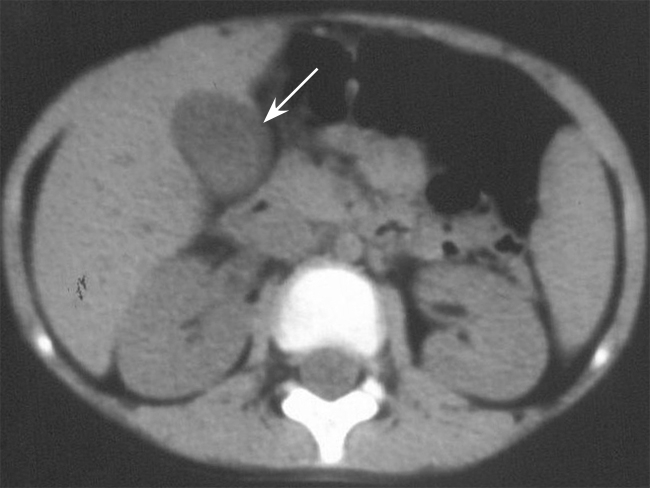

冠状动脉发育异常儿童暴发性心肌炎误诊为急性胆囊炎死亡1例

Death from Misdiagnosis of Fulminant Myocarditis in Children Due to Anomalous of Left Coronary Artery as Acute Cholecystitis: A Case Report